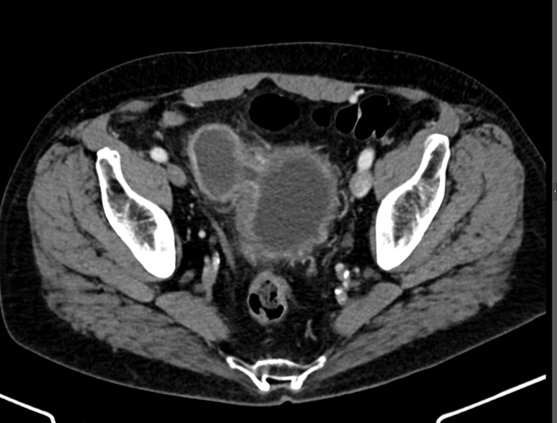

This condition was seen in this recently postpartum 28 year old woman who has pelvic pain.

What is osteitis condensans ilii?